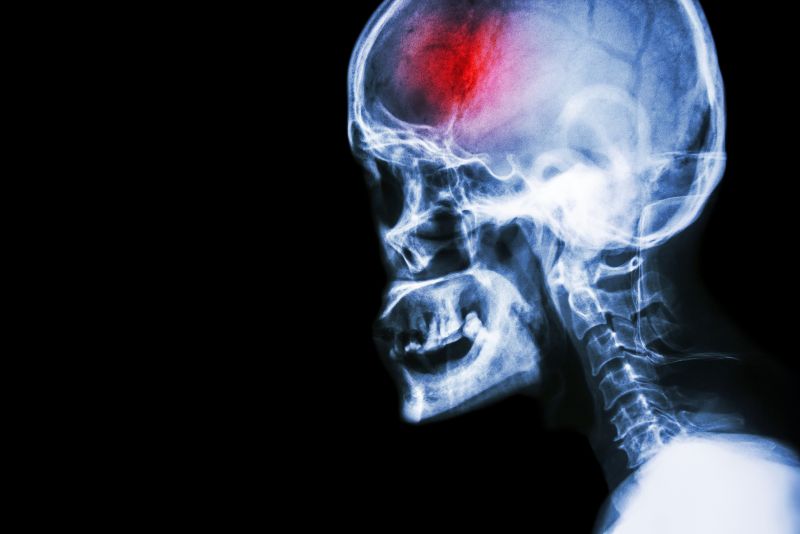

What is a stroke?

A stroke (previously known as a cerebrovascular accident) when there is a decreased flow of blood to the brain from either a blockage in the blood vessels that supply the brain (ischemic stroke), or a bleed from the blood vessels that supply the brain (hemorrhagic stroke). When the blood flow to the brain is blocked it prevents the brain from getting the needed oxygen and nutrients to function. Without oxygen the brain cells can be permanently damaged or die and the physical and mental functions related to that area of the brain will be affected. A stroke is a medical emergency and rapid treatment is crucial to decreasing the damage caused by a stroke.

Computed Tomography (CT) scan and/or Magnetic Resonance Imaging (MRI) scan: These tests are done on your brain and used to locate the exact location of the stroke and to determine if it has been caused by a blockage or a bleed. These tests can also help rule out other conditions that may be causing symptoms, such as an infection or a brain tumour